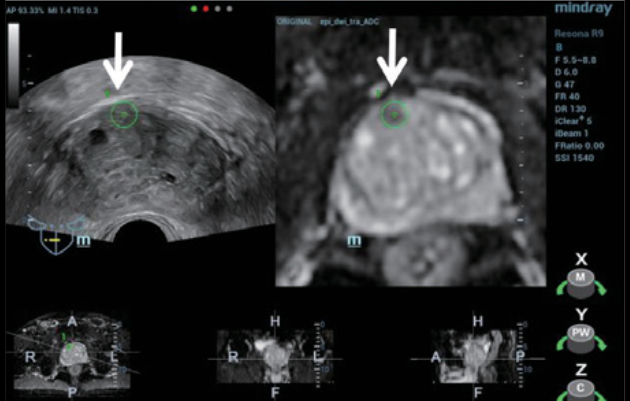

Step 1:???? MRI sequence(Figure 2) ?? ? Resona 9? ??? ??? ??? ??? ??? import ?????.

Step 2:??????? iFusion ?????? ???? TRUS/MRI ???? ?? ? ??(Figure 3) ?? ?? ???(Figure 4).

Step 3:???? ??? ???? ?? ???? ??? ?? MRI ??(Figure 5)? ???? ??? ?? ???(CEUS)? ??????.

Step 4:?TRUS/MRI ?? ??? 12 points systemic needle ????? ??? ? ???? ??? 3??? ??? ??? ?? ????? ???????.